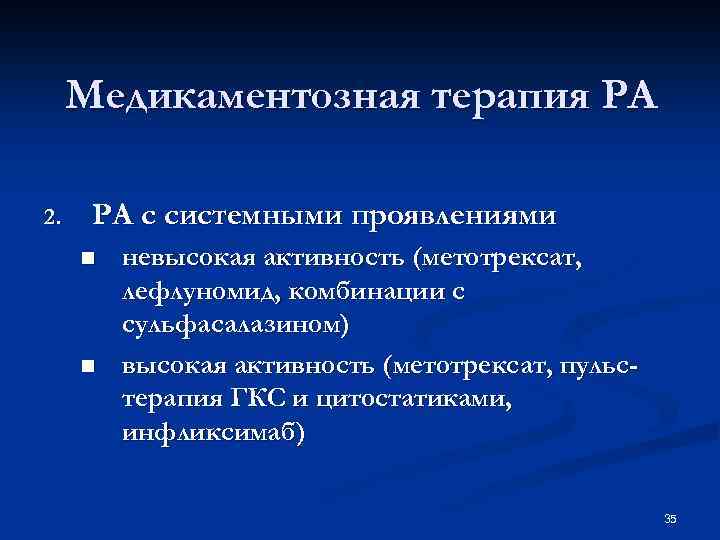

Медикаментозная терапия РА 2. РА с системными проявлениями n n невысокая активность (метотрексат, лефлуномид, комбинации с сульфасалазином) высокая активность (метотрексат, пульстерапия ГКС и цитостатиками, инфликсимаб) 35

Медикаментозная терапия РА 2. РА с системными проявлениями n n невысокая активность (метотрексат, лефлуномид, комбинации с сульфасалазином) высокая активность (метотрексат, пульстерапия ГКС и цитостатиками, инфликсимаб) 35